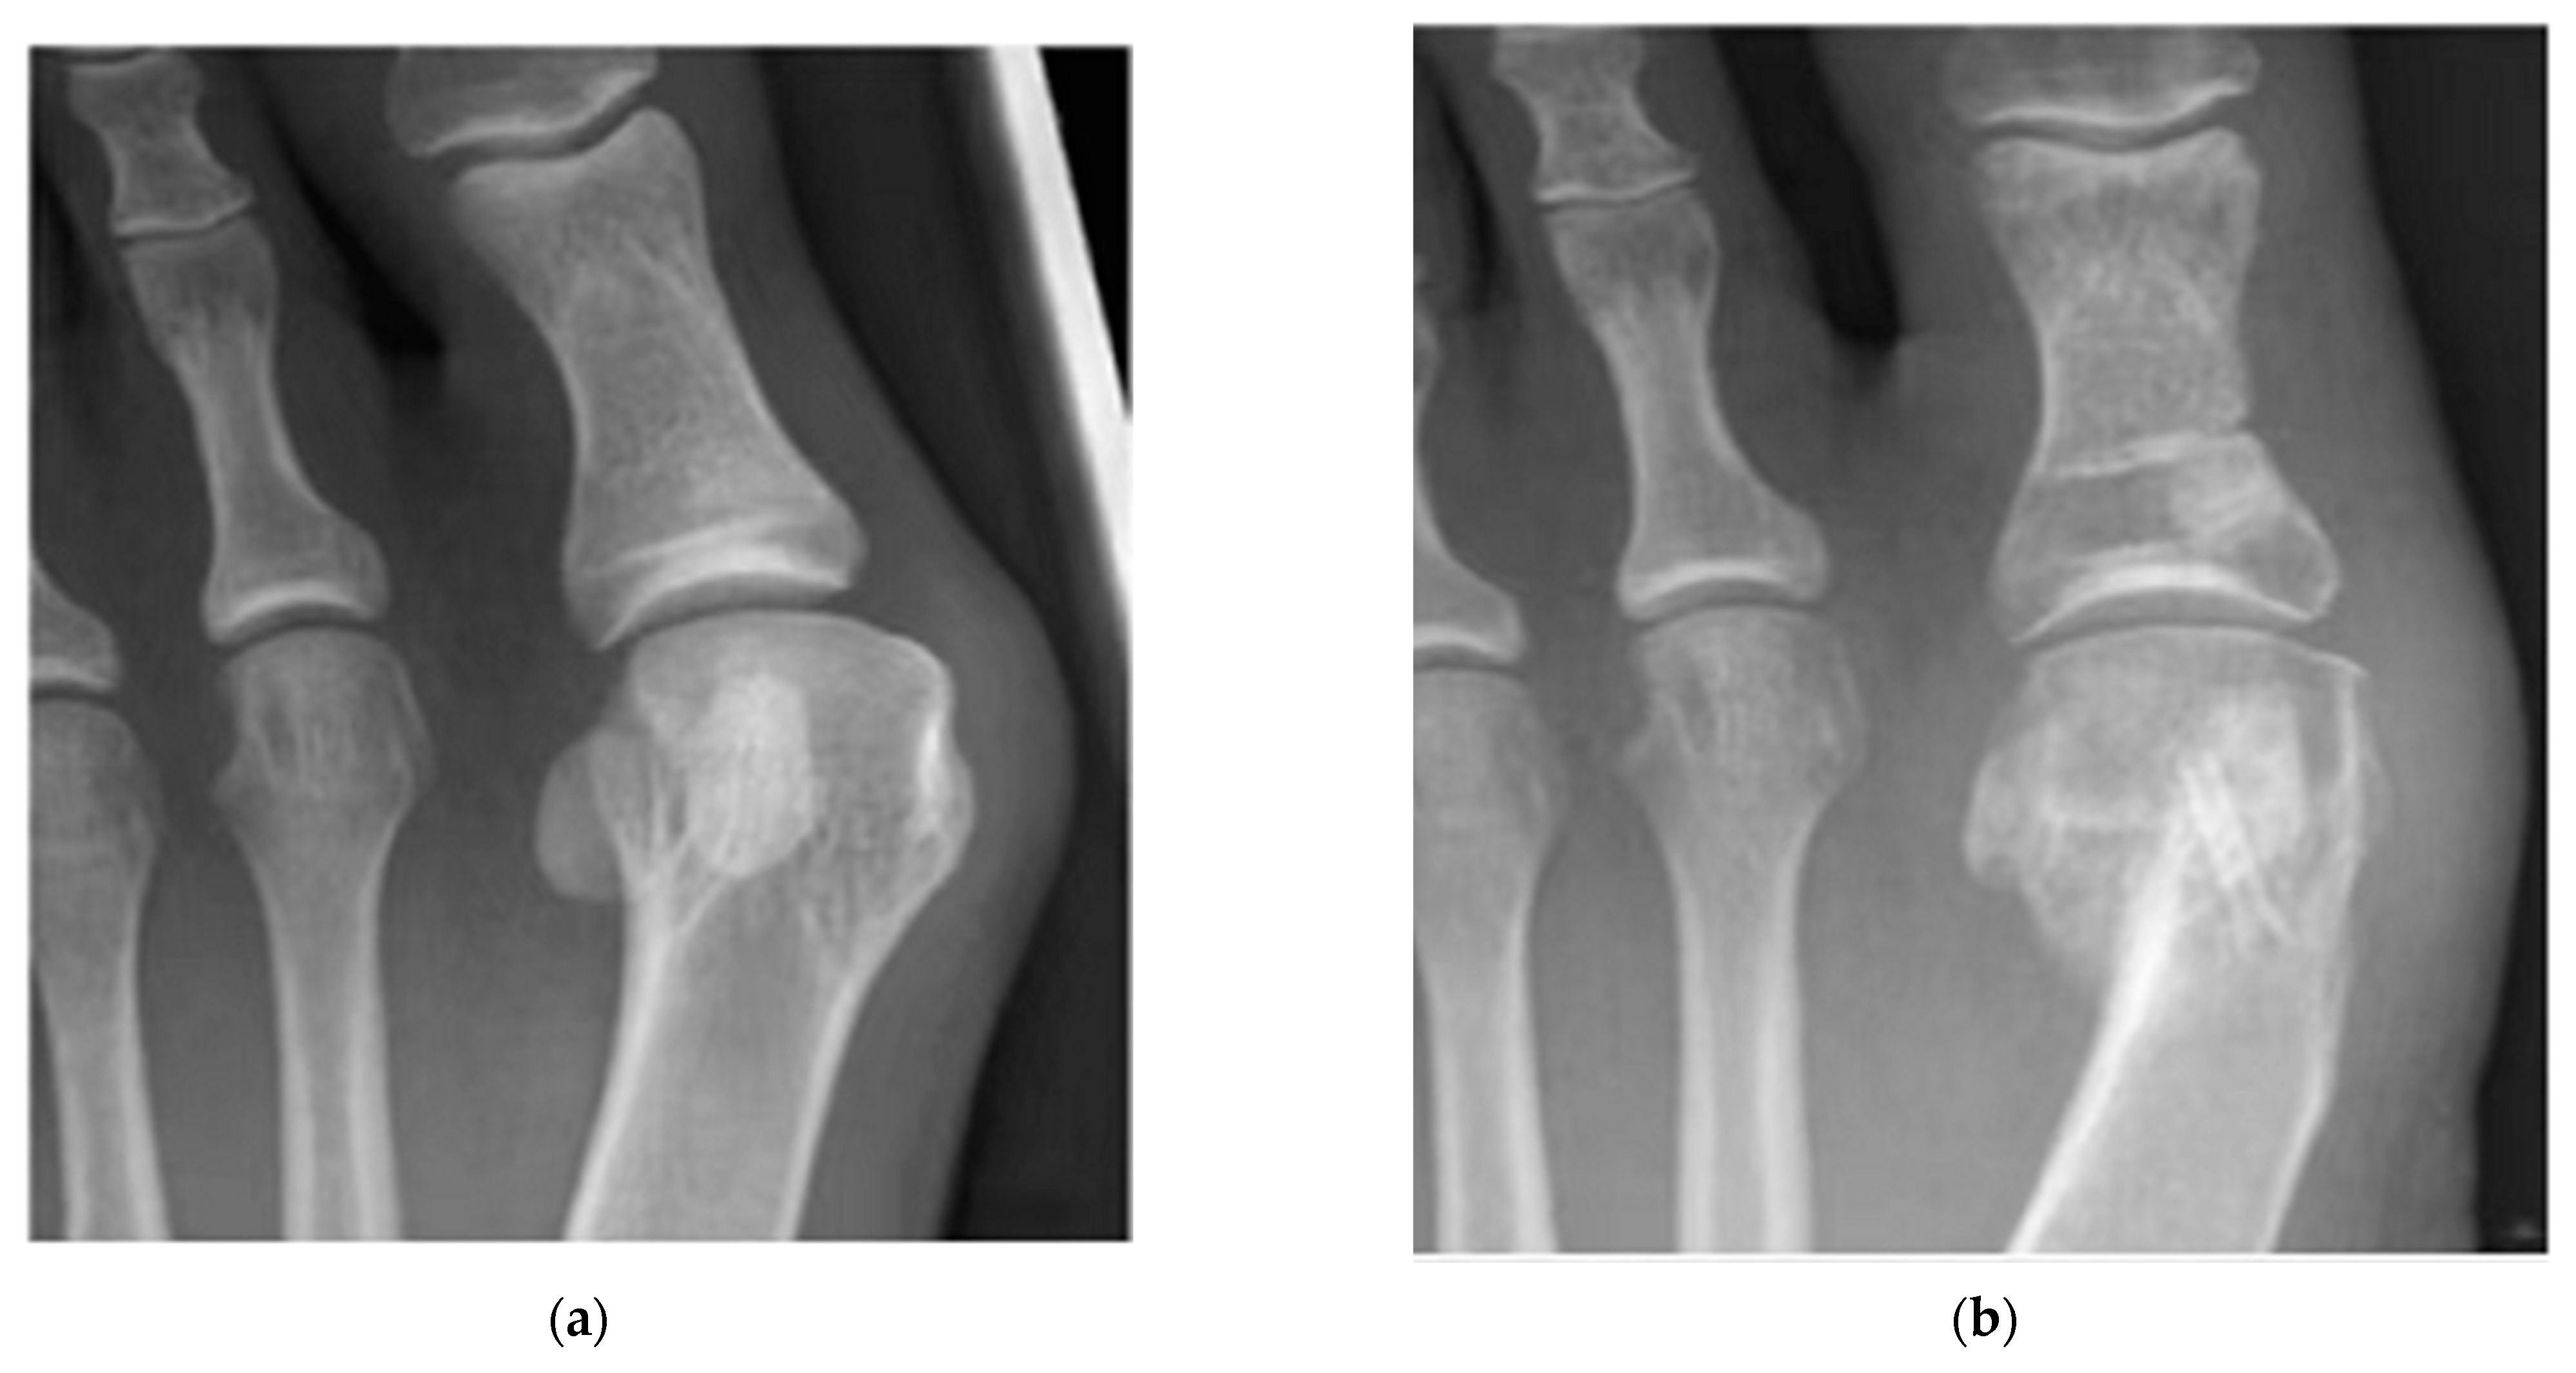

- Lee, J.W.; Han, H.S.; Han, K.J.; Park, J.; Jeon, H.; Ok, M.R.; Seok, H.K.; Ahn, J.P.; Lee, K.E.; Lee, D.H.; et al. Long-Term Clinical Study and Multiscale Analysis of in Vivo Biodegradation Mechanism of Mg Alloy. Proc. Natl. Acad. Sci. USA 2016, 113, 716–721. [Google Scholar] [CrossRef]

- Niu, J.; Xiong, M.; Guan, X.; Zhang, J.; Huang, H.; Pei, J.; Yuan, G. The in Vivo Degradation and Bone-Implant Interface of Mg-Nd-Zn-Zr Alloy Screws: 18 Months Post-Operation Results. Corros. Sci. 2016, 113, 183–187. [Google Scholar] [CrossRef]